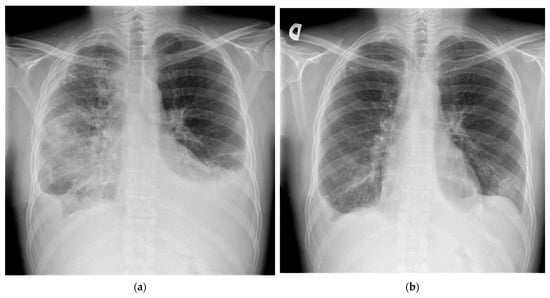

2. Case Report